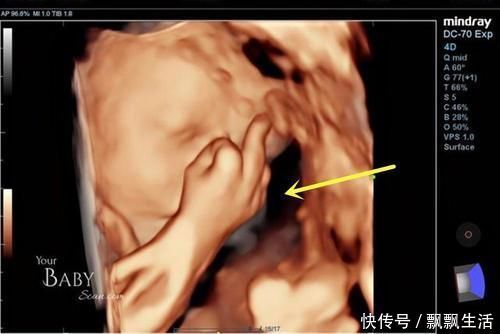

英国孕38周孕妈做彩超,宝宝在肚子里各种搞怪!?

英国的一位孕妈在怀孕38周时去做彩超,在显像下看到了宝宝的可爱样子,宝宝一会儿自己竖中指玩,一会儿又打哈欠,挡着脸玩起来了“捉迷藏”……

文章插图

由于这是他们的第一个宝宝,看到宝宝的这些神奇举动很兴奋,而且明显的看得出,胎儿已经是个“小宝宝”的样子了,而且在妈妈肚子里还很淘气。